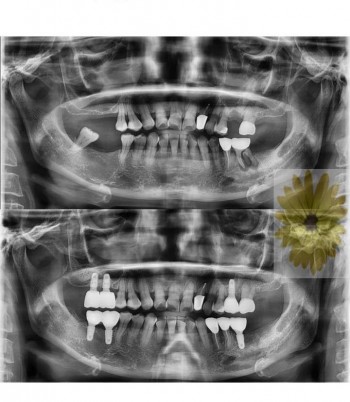

민들레치과 치료 전후사례